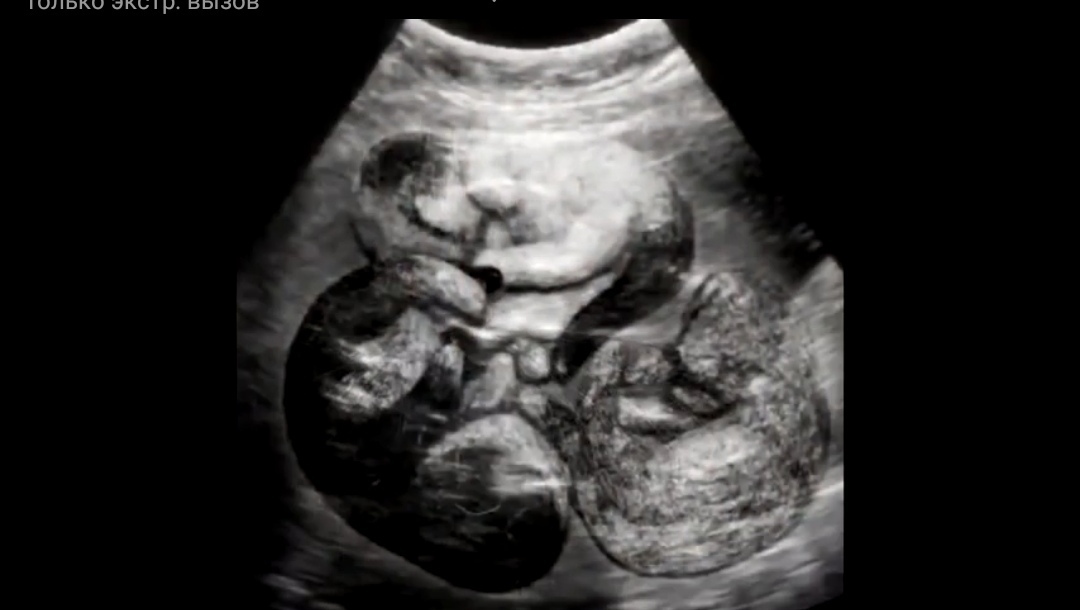

Узи! Скомандовал он... Обследование показало, что кошка беременна,

внутри шевелятся трое котят, уже сформированные лапки,

хвостик и ушки. Все на месте... Вон отсюда! Живодеры! Не